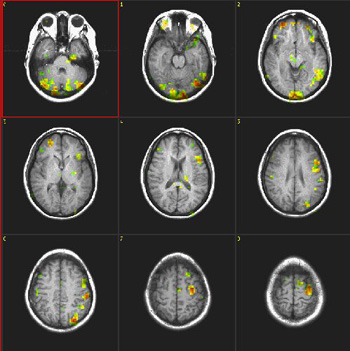

| Activación |

El hemisferio izquierdo muestra activación predominante. Se activaron las siguientes áreas: Área de Broca, porción posterior izquierda de las circunvoluciones temporales inferiores y medias (área 37 de Brodmann), parietal izquierdo y corteza premotora izquierda. Se observa una amplia activación en la cara inferior de los lóbulos occipitales. La activación principal en la derecha está ubicada en la cara inferior del lóbulo frontal (área 11 de Brodmann), un hallazgo observado constantemente en este paradigma. |